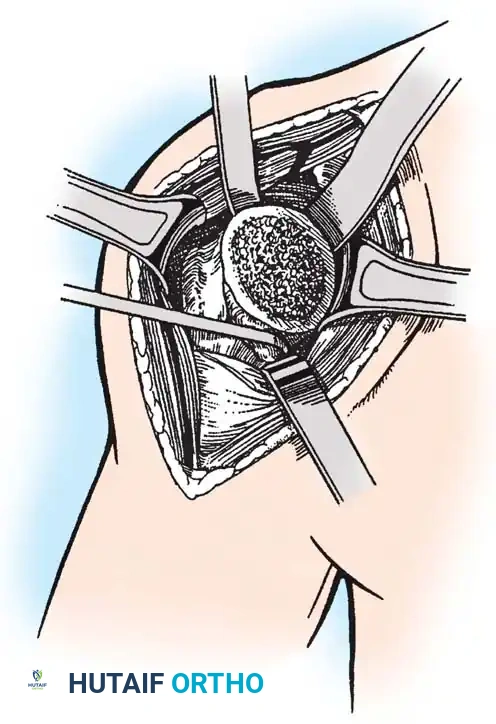

4. Glenoid Preparation

Excellent exposure is critical. Release the inferior capsule completely from the glenoid rim.

* Identify the center point of the glenoid.

* Perform concentric reaming to correct version and create a bleeding bone bed.

* Pitfall: Avoid excessive reaming, which penetrates the dense subchondral bone plate and enters the weaker cancellous vault, leading to catastrophic early subsidence.

Cement the all-polyethylene glenoid component using pulsatile lavage, meticulous drying, and pressurization techniques.